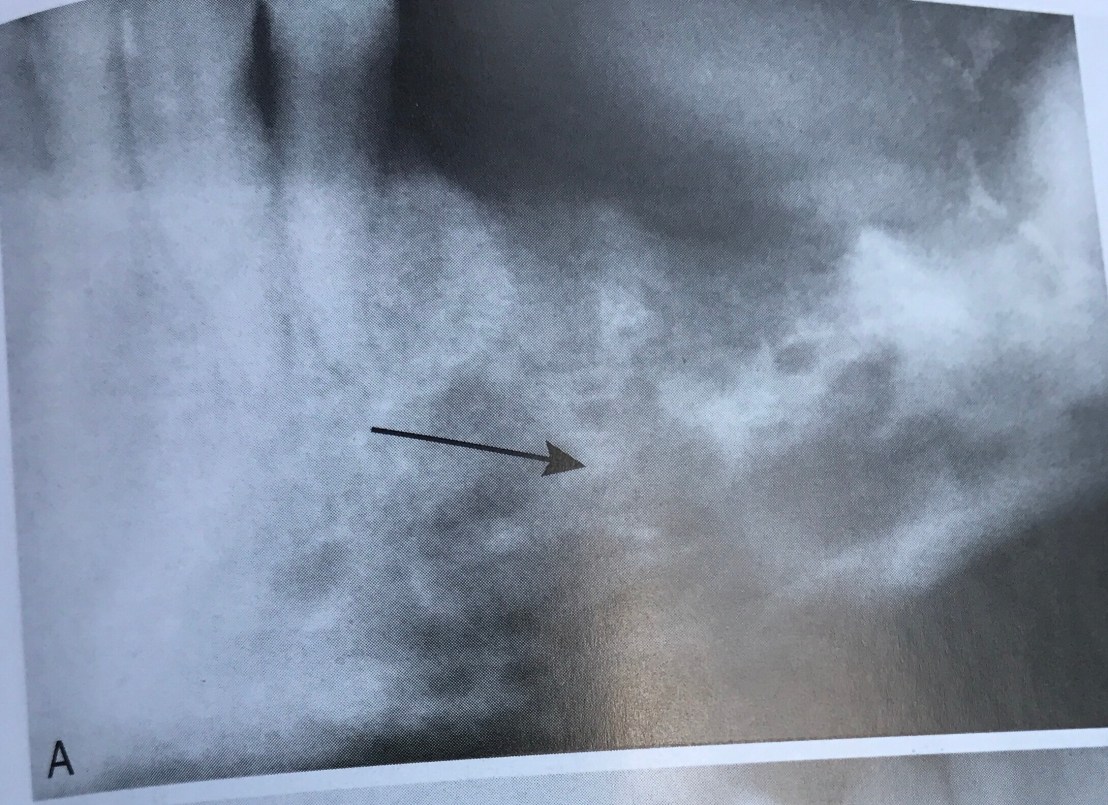

Film แสดงลักษณะของ Osteomyelitis ที่มี Osteolytic changes

รูปแสดงการเกิด multiple sinus tracts ของ Osteomyelitis จาก Subperiosteal implant

รูป A แสดงการเกิด Cavernous sinus thrombosis เคสนี้เริ่มมีอาการ 72 ชม.หลังทำฟัน

อาการเริ่มด้วย ปวดหัวอย่างรุนแรง มีไข้สูง หนาวสั่น ชาที่เปลือกตาบนและล่าง ไม่สามารถเคลื่อนตาขวาได้ มีจุดเลือดออกที่ผิวหนังบริเวณจมูก

ส่วนรูป B คือ Cavernous sinus thrombosis infection เช่นกัน มีอาการบวมรอบตา ข้างที่ infected